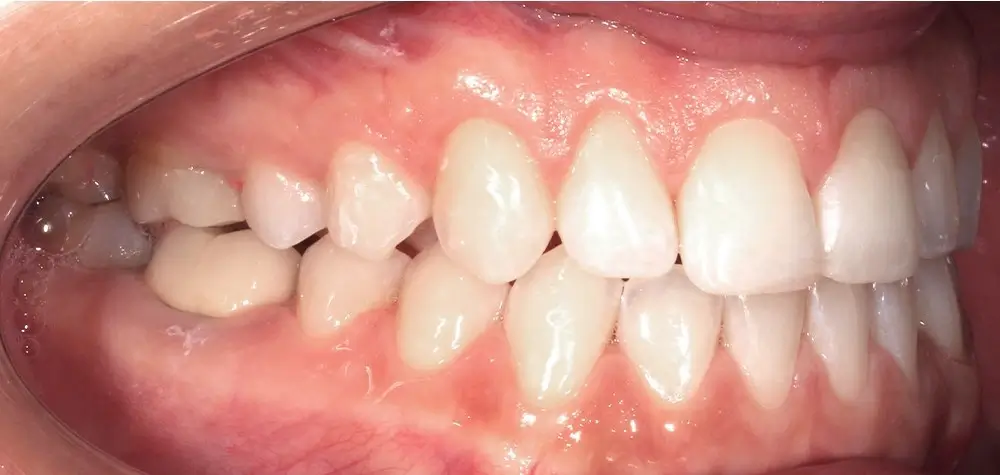

Открытый прикус - Кейс 5

Эффективность устранения дефекта прикуса посредством элайнеров FlexiLigner.

20

Количество кап НЧ

16

Количество кап ВЧ